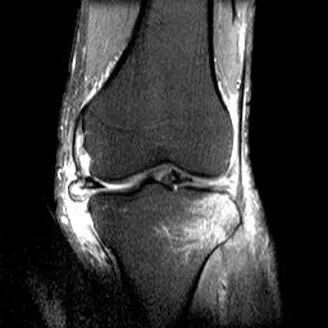

半月板水平撕裂

1、水平撕裂

2、较少见3、III级高信号与胫骨平台平行,到达半月板的游离缘或一侧关节面

(半月板水平撕裂)